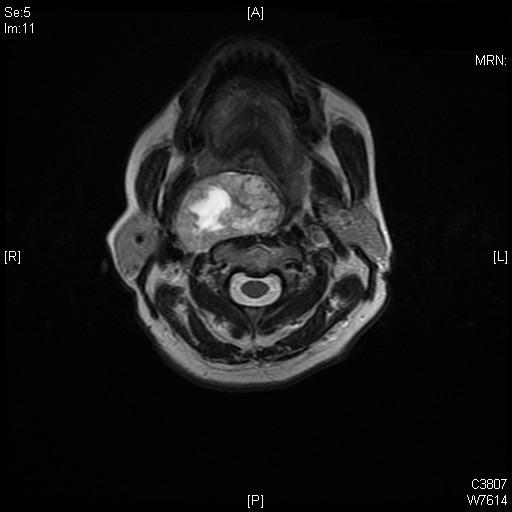

Schwanoma

Doente do sexo femenino de 59 anos, com massa volumosa massa do espaço parafaríngeo.

Schwanoma parafaríngeo direito que contacta e desvia lateralmente a artéria carótida interna e a veia jugular dta.